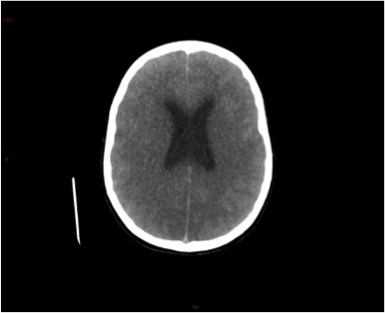

Un scanner cérébral sans injection est réalisé. Les reformations axiales vous sont présentées.

Question 10 : Ce scanner présente :

Les espaces sous sous-arachnoidiens ne sont plus visibles. Ne pas confondre la substance grise qui arrive au contact des os du crâne, avec une hyperdensité spontanée méningée.

Le volume des ventricules paraît faussement augmenté du fait de l’effacement diffus des sillons corticaux.

Qui traduit une augmentation du volume cérébral.

Les sinus veineux sont normalement hyperdenses sans argument pour une thrombose veineuse cérébrale.

Aucun des deux hémisphères cérébraux ne passe sous la faux du cerveau. L’augmentation du volume cérébral est diffuse.

Effacement diffus des sillons corticaux avec début de dédifférenciation des de la substance blanche - substance grise notamment des noyaux centraux. Cela traduit un œdème cérébral diffus secondaire à un bas débit cérébral.

Vous retenez donc le diagnostic d’œdème cérébral diffus. Le patient ne se réveille toujours pas et présente sur un scanner de contrôle une majoration de cet œdème et un engagement des amygdales cérébelleuses.